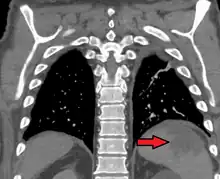

| Splenic infarct seen on CT | |

An abdominal CT scan is the most commonly used modality to confirm the diagnosis,[3] although abdominal ultrasound can also contribute.[5][6][7]